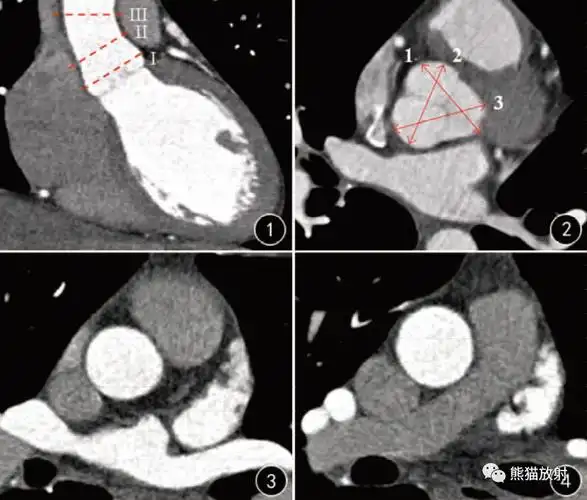

当胸部ct发现有主动脉增宽,你会怎么处理? [病例帖]

胸ct平扫示:①升主动脉明显增粗;②心影增大;不除外心包少量积液,请

升主动脉扩张丨阈值,相关因素

患者李坤(化名),53岁,因"胸痛17小时"来院就诊,入院后检查主动脉cta